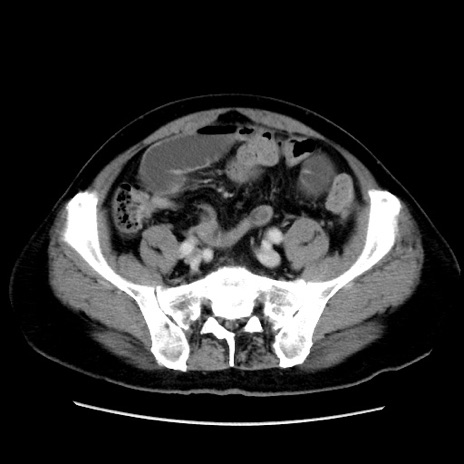

症例16(横断像)

冠状断像

【症例】 70歳代男性

【主訴】 腹痛、嘔吐

【現病歴】 約1ヶ月前より間欠的に腹痛と嘔吐あり、当院消化器内科を受診したところCTで多発する肝臓のLDAを指摘され、精査中であった。以降は消化器症状は安定していたが、2日前より嘔気と腹痛があり、同日より排便・排ガスが消失した。改善認めず、 本日、救急外来を受診した。

【既往歴】 大腸ポリープ切除後。

【身体所見】意識清明・会話良好、BT 36.3℃、BP 127/80mmHg、 P 80bpm、腹部:膨満あり、平坦・軟、上腹部正中および下腹部正中に圧痛あり、反跳痛なし、筋性防御なし。

【データ】WBC 7200、CRP 0.77